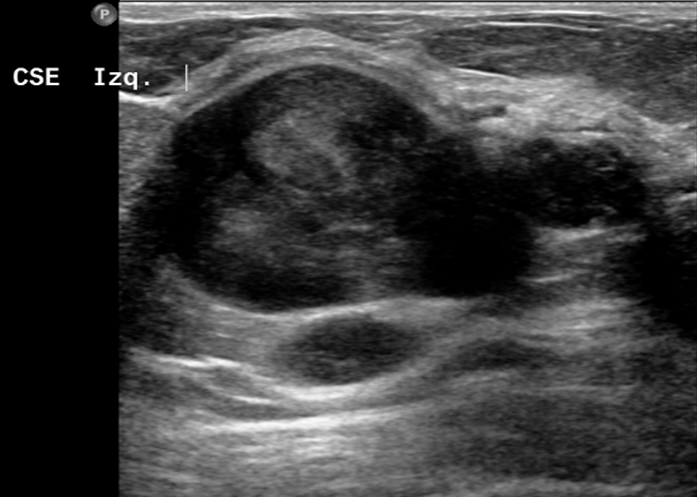

La técnica complementaria de elección es la ecografía, ya que la mamografía es incapaz de distinguir si el contenido del nódulo es líquido o sólido. Gracias a la ecografía podemos dirigir a tiempo real una biopsia por agujar gruesa (BAG).

Al realizar la ecografía obtenemos esta imagen: